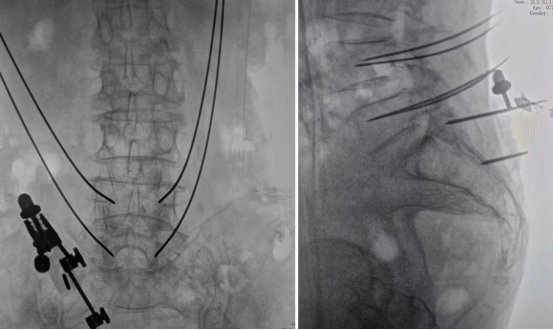

The robotic arm moved to the planned entry points, with its guide sleeve perfectly aligned with the pre-planned trajectory. The surgeon then drilled four Kirschner wires through this guide.

After intraoperative verification confirmed accurate positioning, four pedicle screws were placed. Compared to the traditional freehand technique, robot assistance eliminates deviations caused by reliance on subjective tactile feedback, significantly enhancing the accuracy of screw placement.